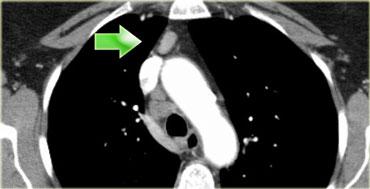

Bên trái là hình ảnh dưới mức carina.

Bên phải thực quản là một hạch nhóm 8.

Bên trái là hình ảnh PET cho thấy sự hấp thu FDG tại hạch nhóm 8.

Trên hình CT tương ứng, hạch không to (mũi tên xanh).

Khả năng đây là hạch di căn là cực kỳ cao, vì độ đặc hiệu của PET đối với các hạch không to cao hơn so với các hạch đã to.